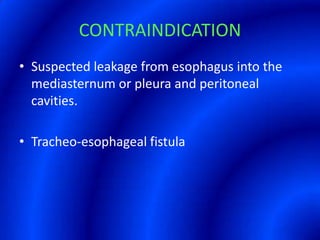

This document provides information about a barium swallow procedure. It begins with an introduction and overview of the embryology and anatomy of the pharynx and esophagus. It then describes the procedure itself, including preparation, technique, views obtained, and indications. Specific conditions that may be examined include pharyngeal and esophageal webs, foreign body impaction, scleroderma, dysphagia, mediastinal masses, and carcinoma. Diagrams are provided to illustrate normal anatomy and various pathological findings.